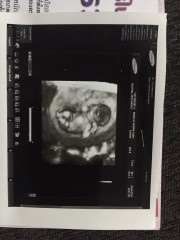

ตอน13+3ค่ะตอนนี้28+1

13วีคคร่า